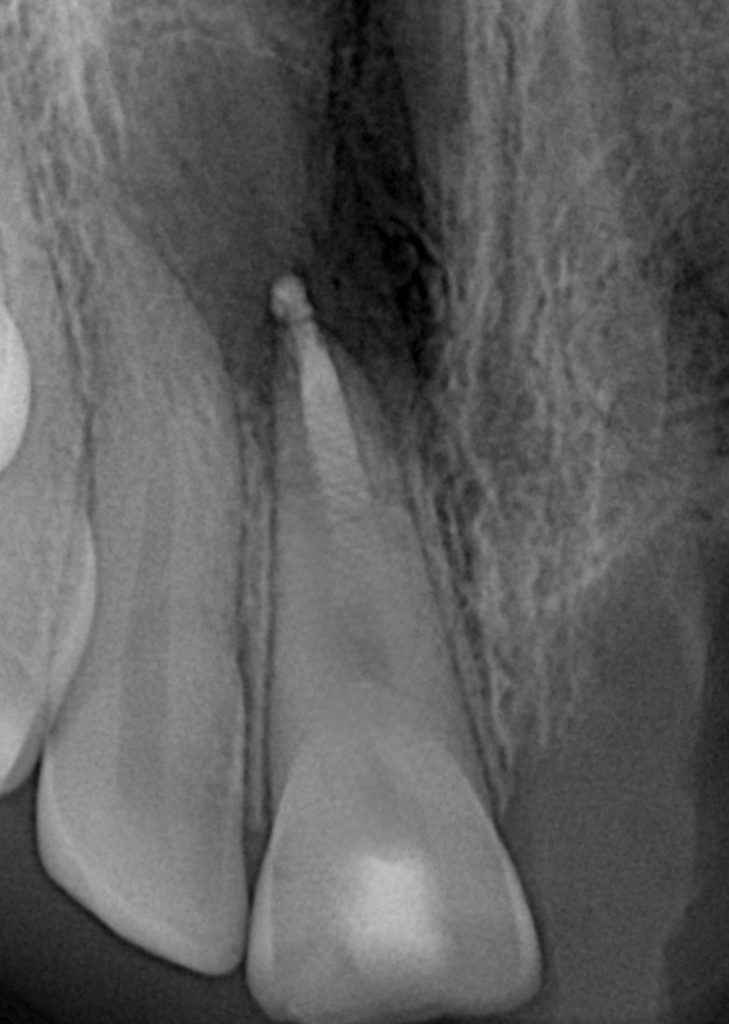

After verifying the apical barrier radiographically, BioSeal bioceramic material was used to seal the remaining canal space coronally.

Step 6 – Coronal Seal

Moist cotton pellet placed temporarily for initial setting of MTA. Access cavity sealed with bonded composite to prevent coronal leakage.

Outcome

•Immediate apical seal achieved

•Root canal system biologically stabilised

•No extrusion or postoperative pain

•Radiographic follow-up scheduled for 3 months